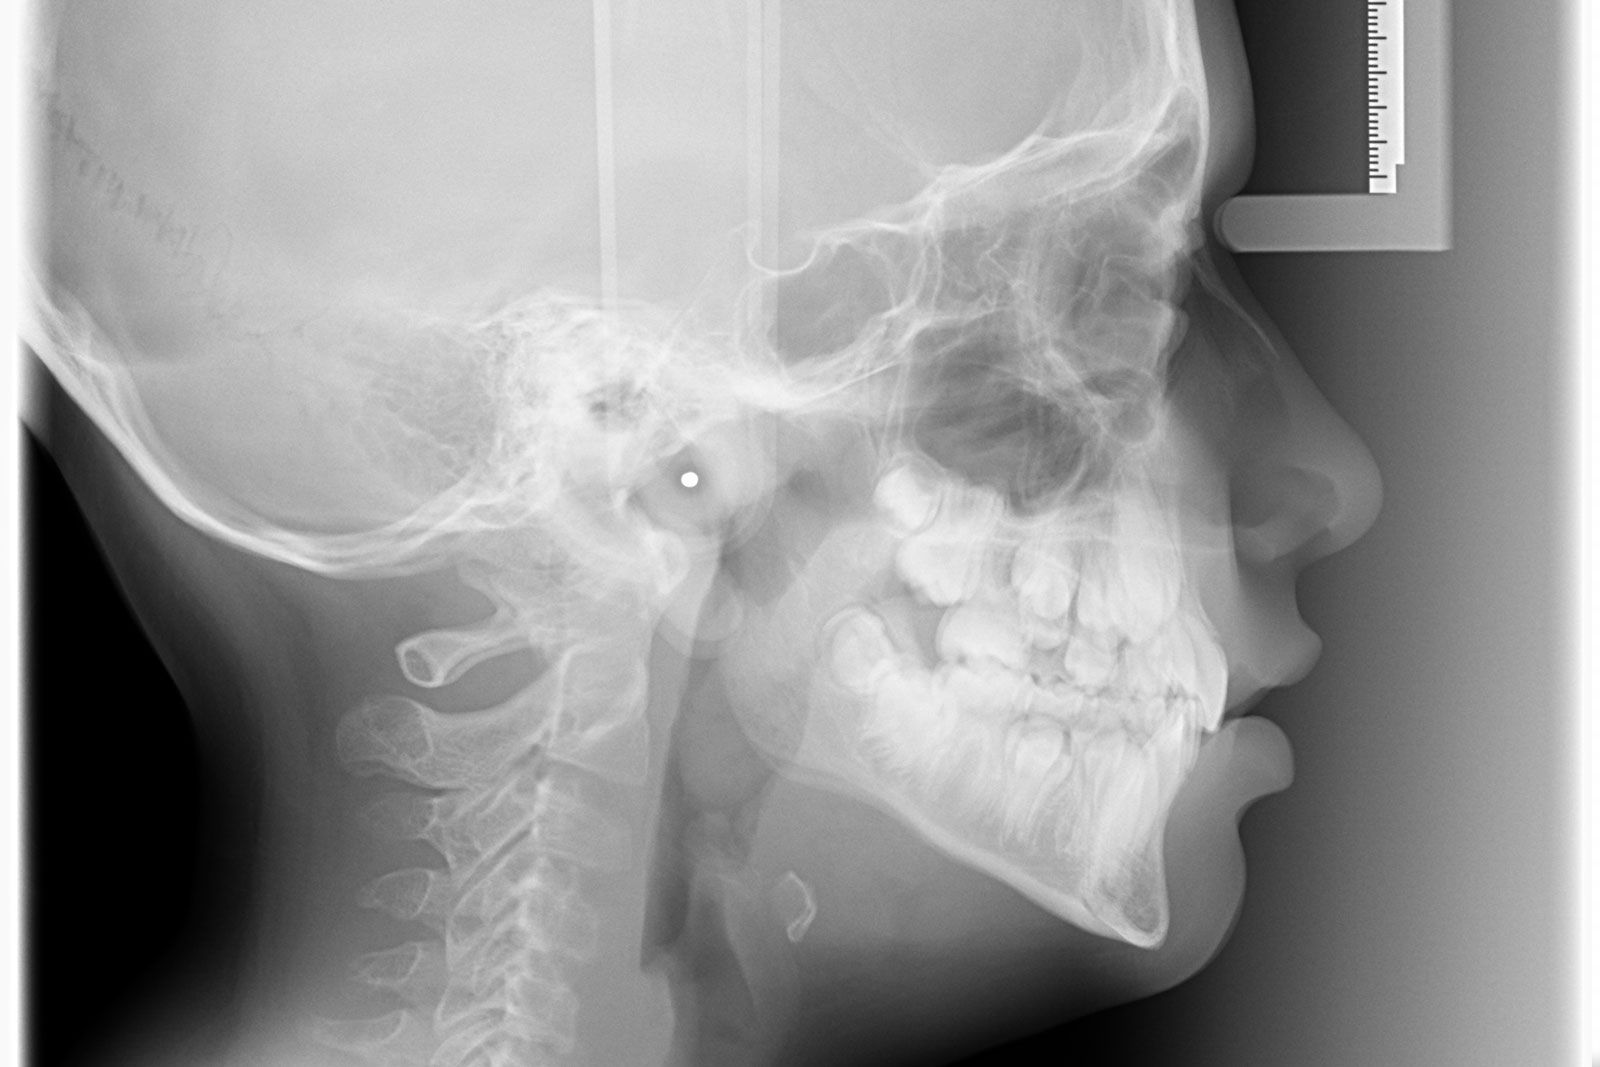

Radiologia Odontoiatrica

La sezione di radiologia odontoiatrica digitale offre servizi all'avanguardia nel campo della Diagnostica per Ortodonzia, Piantologia, Parodontologia, Chirurgia Maxillo - Facciale e Gnatologia.

Aster Diagnostica è dotata di un ortopantomografo digitale diretto, per l'esecuzione dell'ortopanoramica e del telecranio. La tecnologia diretta permette di ottenere immagini di alta qualità diagnostica a fronte di radiazioni contenute.

- Ortopanoramica

- Telecranio